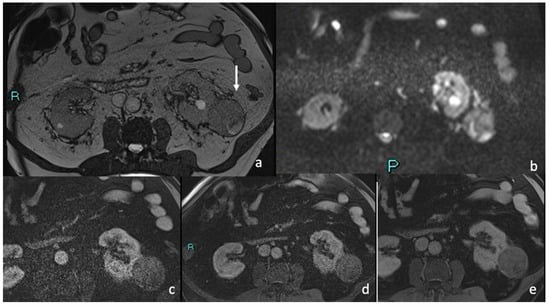

3.4. MRI

Signal Intensity, Homogeneity, and Contrast Enhancement

| MRI FEATURES | % | n. | p Value |

|---|---|---|---|

| 85.2% 14.8% | 23 4 | p < 0.05 p > 0.05 |

| 88.9% 7.4% 3.7% | 24 2 1 | p < 0.05 p > 0.05 p > 0.05 |

| 29.6% 11.1% 59.5% | 8 3 16 | p > 0.05 p > 0.05 p < 0.05 |

| 100% | 27 | p < 0.05 |